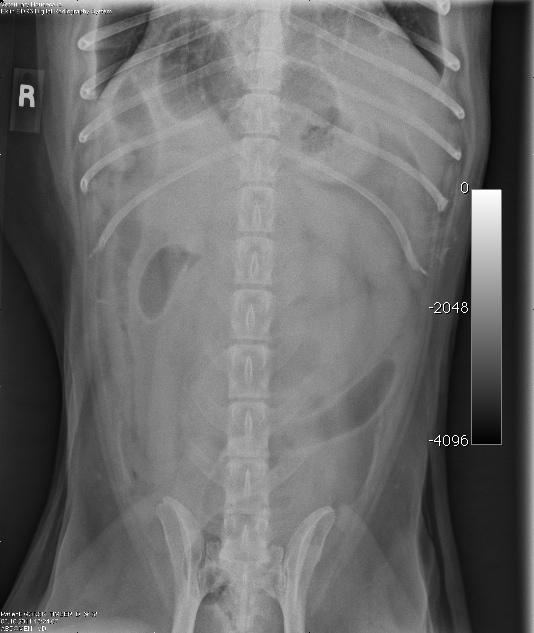

A 10 year-old MN Shepherd mixed dog presented with a 2-3 month history of intermittent vomiting and a more recent anorexia. Abnormalities on physical examination were dehydration and a 3 cm firm left anal sac mass. The only significant finding on CBC and serum biochemistry was hypoalbuminemia. Survey radiographs showed no evidence of pulmonary metastases but revealed excessive pyloric gas pattern with a volume contracted heart.